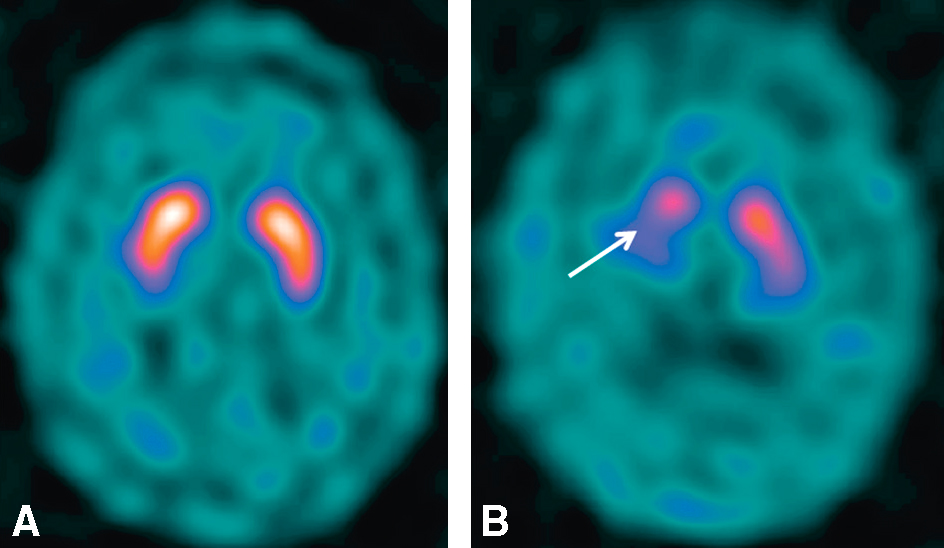

• Figure Une scintigraphie cérébrale au DaTSCAN® (ligand du transporteur de la dopamine, présent sur le neurone présynaptique de la synapse dopaminergique) ou une TEP à la fluoro-dopa ne doivent être effectuées que s’il existe un doute entre un tremblement par-kinsonien lié à une maladie de Parkinson et un tremblement parkinsonien lié aux neuroleptiques (DaTSCAN® anormal avec dénervation dopaminergique nigro-striatale en cas de maladie de Parkinson mais normal en cas de prise d’antipsychotique : fig. 18.2).

Fig. 18.2 Figure Scintigraphie cérébrale au DaTSCAN®.

A. Fixation dopaminergique nigro-striatale normale chez un sujet sain ou dans le cas d’un syndrome parkinsonien lié aux antipsychotiques (de même que dans le tremblement essentiel). B. Dénervation dopaminergique nigro-striatale avec hypofixation bilatérale prédominant à droite (flèche) du DaTSCAN® dans la maladie de Parkinson.